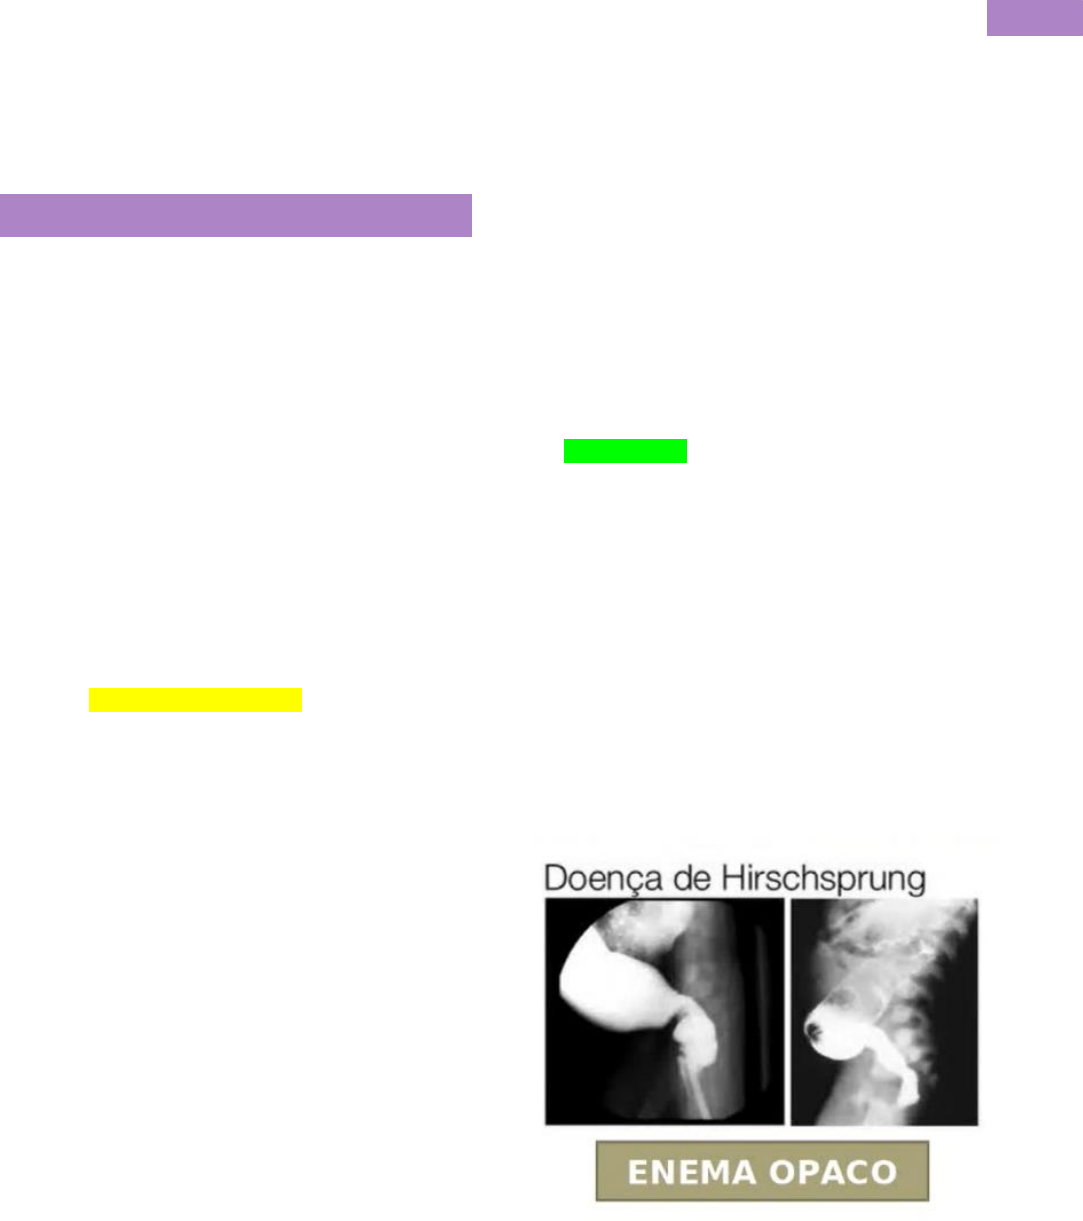

Grátis: Doença de Hirschsprung - Material Claro e Objetivo em PDF para Estudo Rápido

image size: 1620x1620